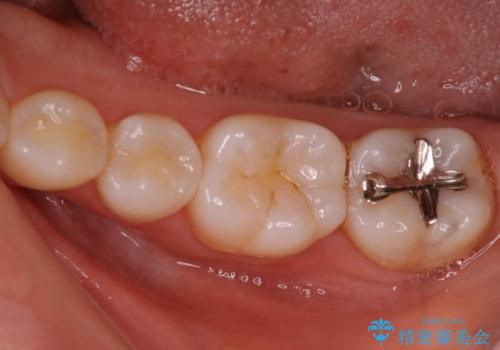

銀歯を白いセラミックに変えたい セラミックインレー

- 銀歯が気になるためやり替えたいとのことで来院されました。

セラミックインレーで治療を行いました。

口の中にチラつく銀歯は適合の良いセラミックインレーでやり替えることで綺麗にやり替えることができます。